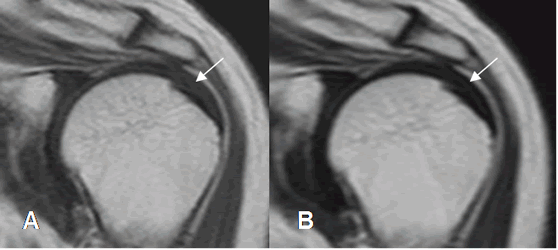

El intervalo rotador es mejor evaluado con las secuencias sagitales. La presencia de líquido en esta región es el principal signo de patología. (9). (Fig 30 y 31).

Fig 30. Intervalo rotador normal.

A: RM coronal en T1 y B: RM sagital en T2. Intervalo normal con la presencia de grasa.

Contiene el ligamento coracohumeral (Flecha delgada) y la cabeza larga del biceps. (Flecha gruesa).

C: Apófisis coracoides. SE: Músculo supraespinoso. SB: Músculo subescapular.

Fig 31. Intervalo anormal.

A y B: RM sagital en STIR. Presencia de líquido y cambios inflamatorios en el intervalo rotador, como hallazgo patológico.